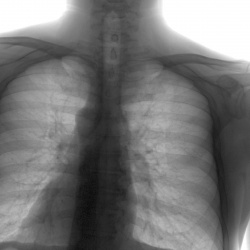

Пациента 70 лет. Две недели назад была температура , перенесла на ногах , что на снимке?